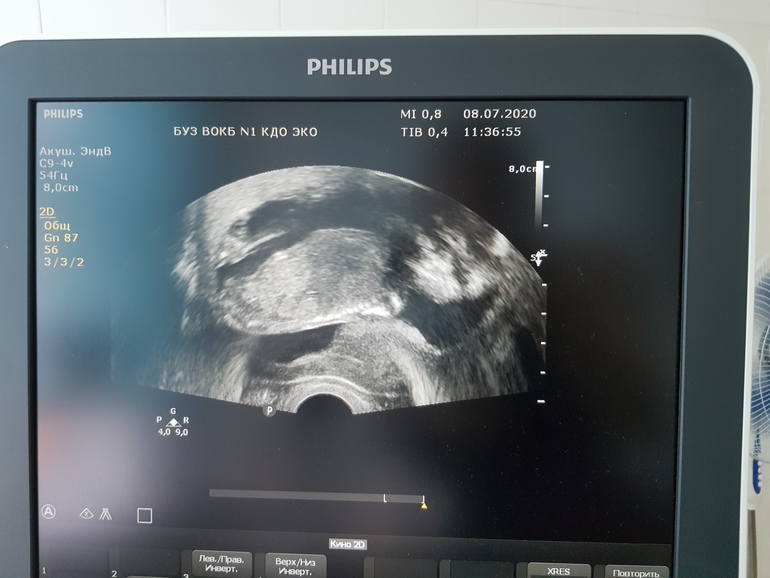

Пол малышаСходила сегодня на очередное УЗИ Сегодня 16.2 в основном смотрели шейку, но я попросила еще раз пол посмотреть, мельком сказала, что похожа на девочку, я попросила хоть картинку мне оставить, я сфоткаю, что бы вам показать))) На ней я особо ничего не вижу, но может есть люди более понимающие))) На скрининге, когда смотрели более подробно, сказали, что 90% девочка))) Как думаете?))

РозовыйПион

Как я поняла

Ребёнок лежит продольно на фото

Внизу более ярким пунктиром - позвоночник

Голова слева , пипка справа, светлый участок туловища заканчивается «Э», это и есть профиль пирожка

Ну как я поняла

Ну может я фантазёр )))

Да девочка ж ) ну на таком сроке уже бы пипюн нашли б )

А мне кажется голова справа🤣 Ды, что то узистка не очень уверенно сказала... Вот и я не уверенна. Больше уверенна в словах той узистки, которая делала скрининг, там и изображение было в разы четче))

Я и тут девочку вижу ! И профиль какой то мягкий , как для девочки )